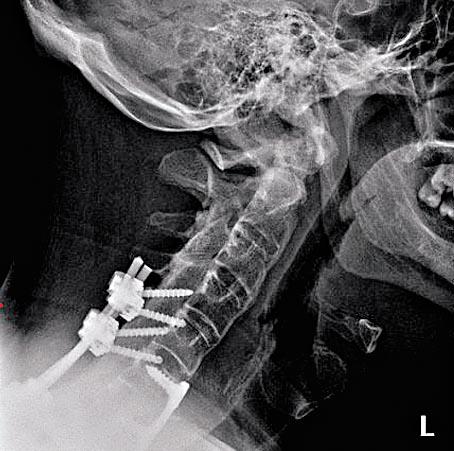

里卡德回家後依然劇痛難當,半小時後已要再找醫生,但醫生一直以扭傷的方法來治療,即使後來定期做物理治療,也幫不上忙,他只好再次入院,接受密集的物理治療,這時醫生才發現,原來他的頸不是扭傷,而是斷了。因醫生頸扭傷和斷頸不分,結果害他白白誤診了五個月。

「難以置信,你怎可能把這些東西搞錯?」真相大白後,里卡德五個月內接受了三次手術,「醫生告訴我,如果早點發現,我便不用做這麼多手術」。